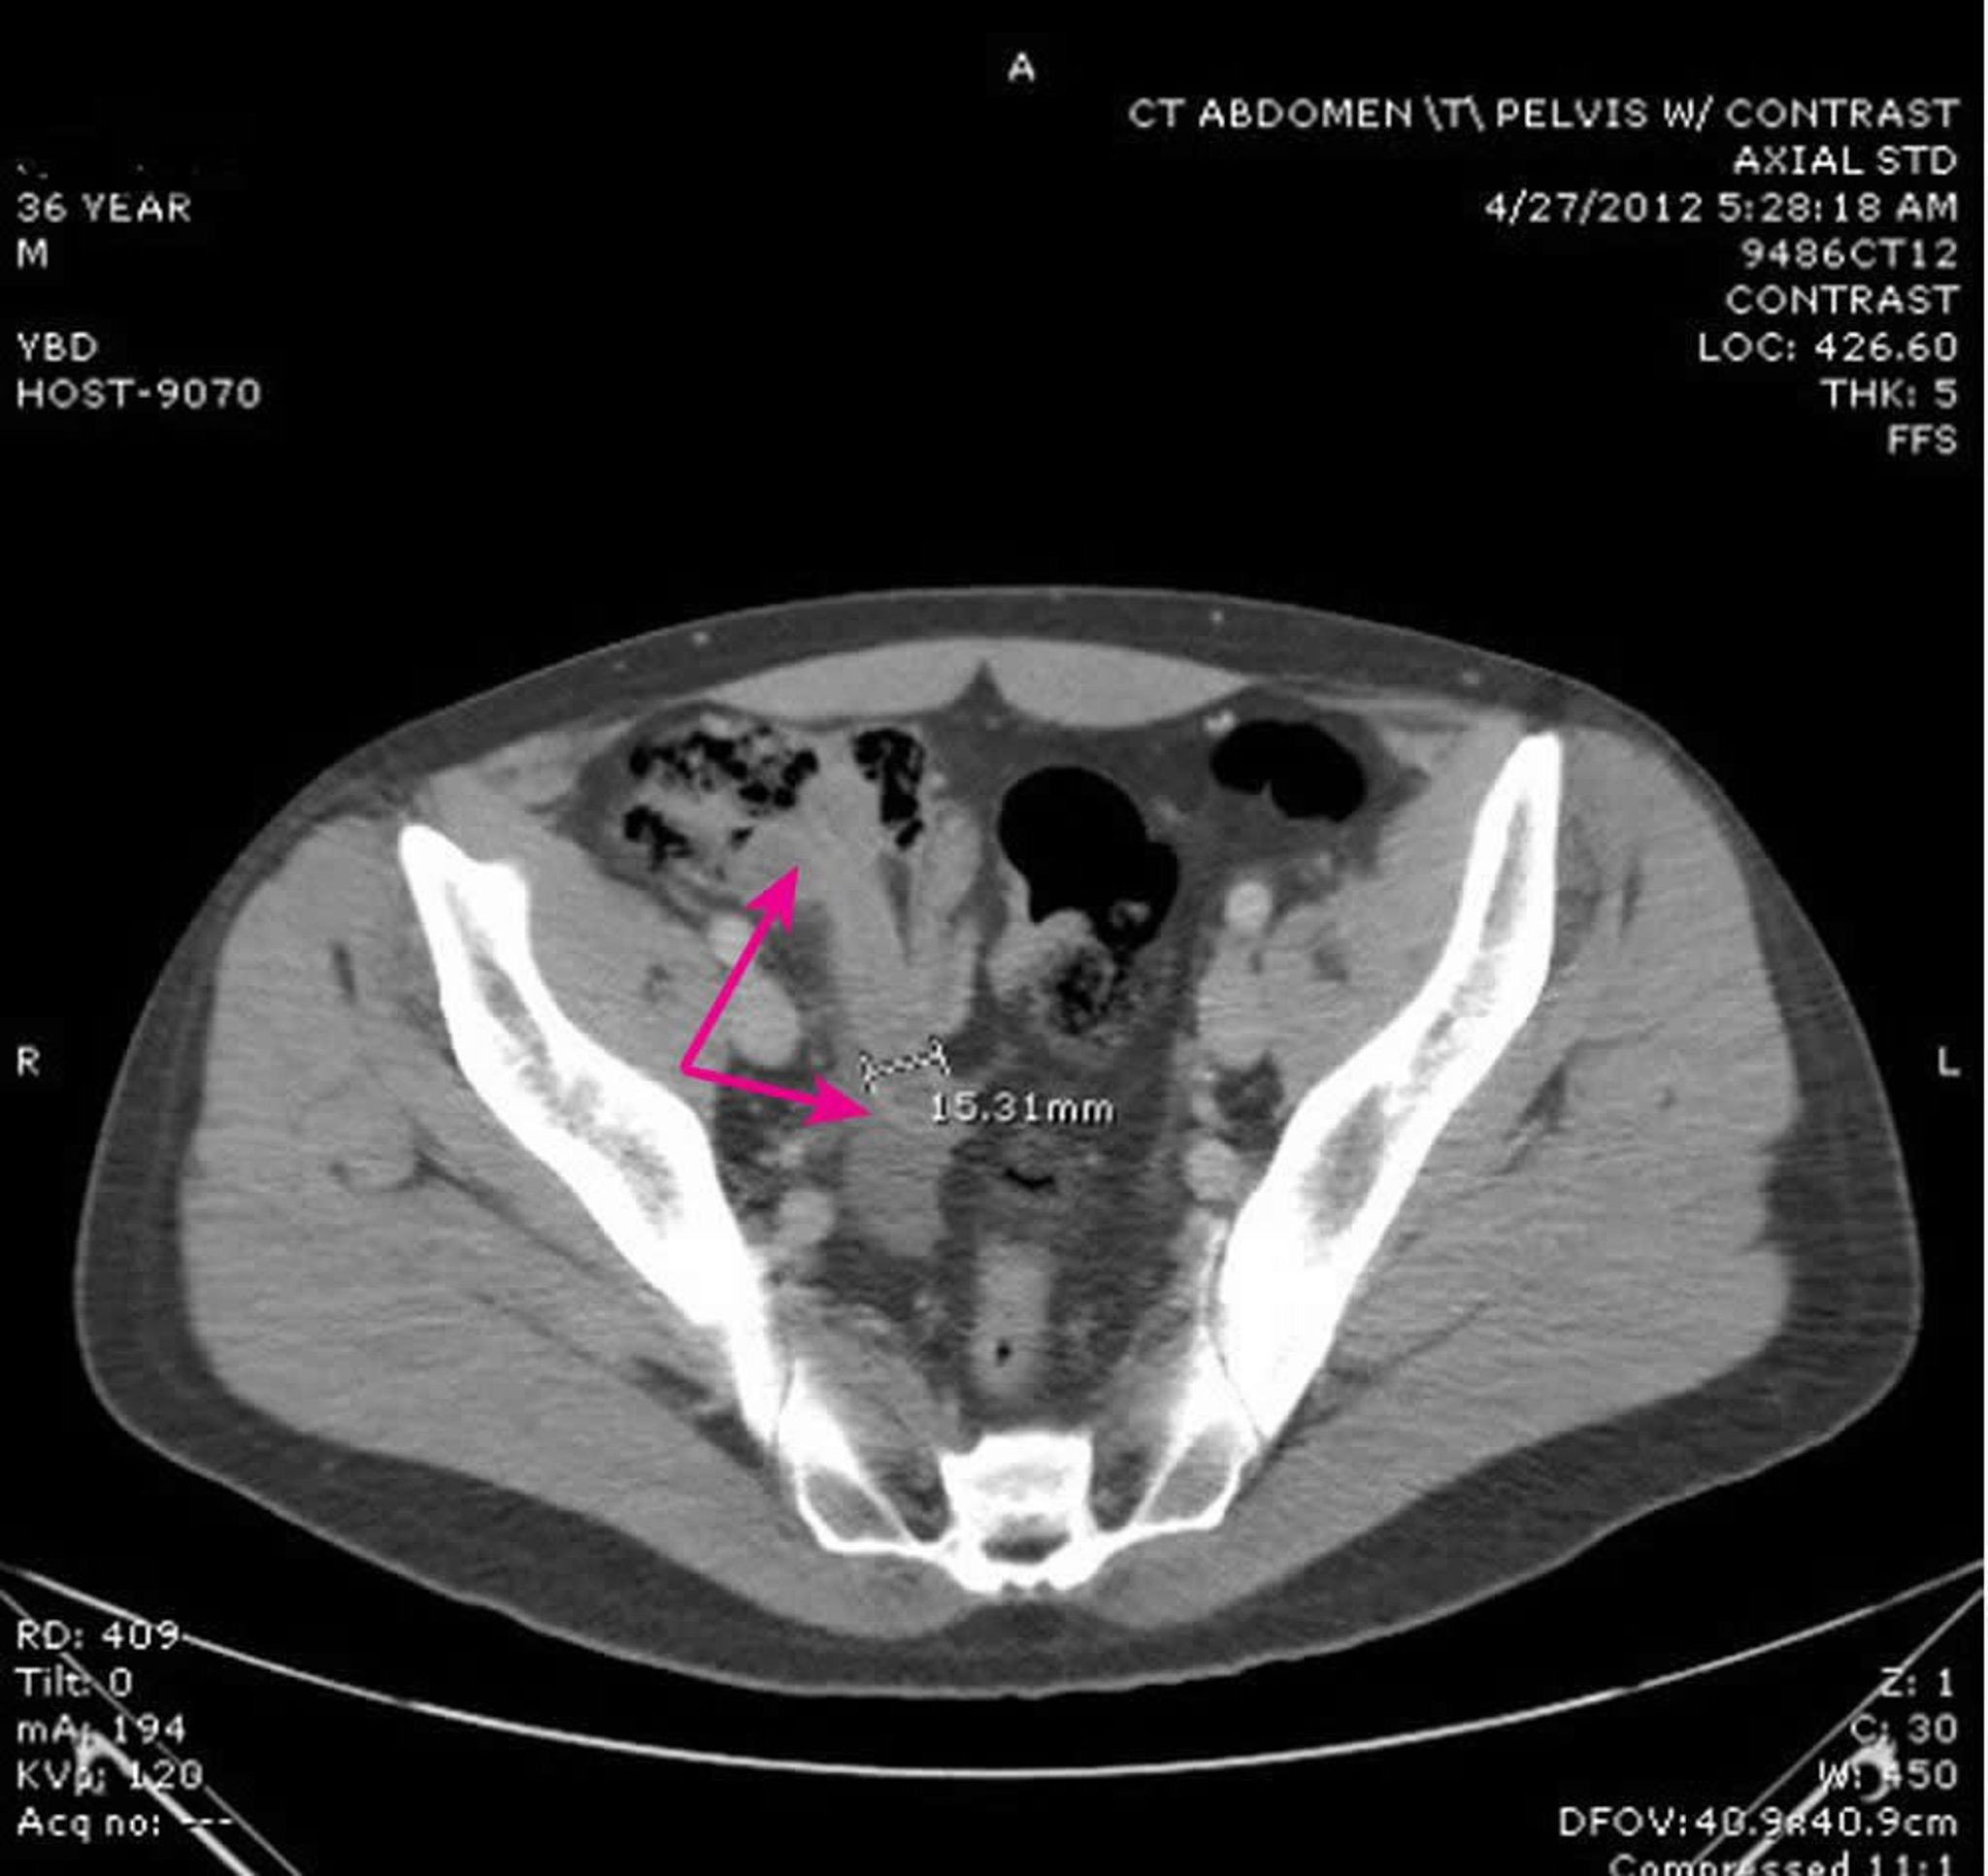

Questa immagine mostra un'appendice dilatata con pareti spesse (frecce) di 15,31 mm di diametro con cambiamenti infiammatori attorno.

Image provided by Parswa Ansari, MD.